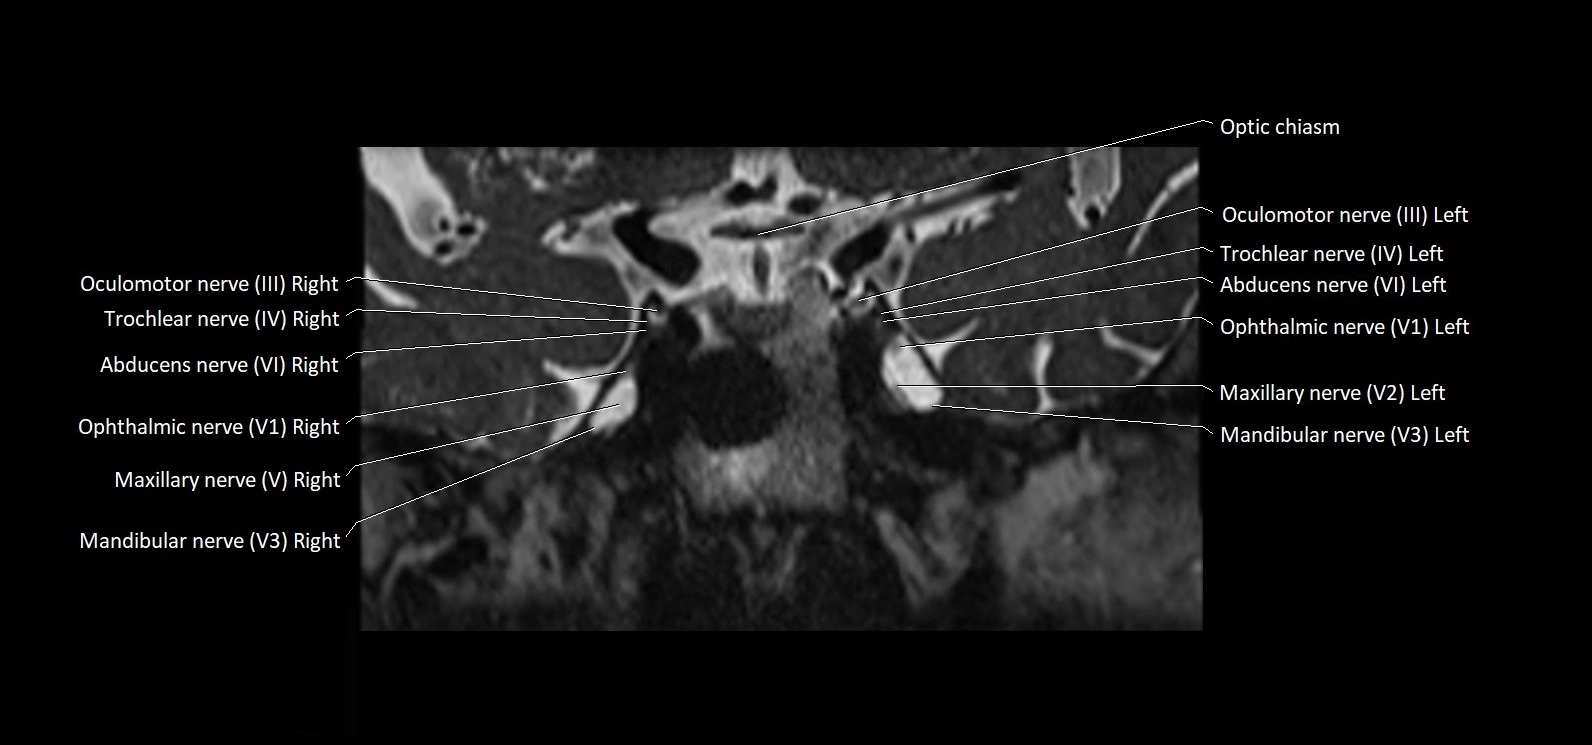

MRI Appearance

• The abducens nerve is a small, thin, linear structure

• Best visualized on high-resolution T2-weighted 3D MRI sequences (e.g., FIESTA or CISS)

• Seen as a hypointense (dark) line running from the brainstem at the pontomedullary junction, traversing the prepontine cistern, and entering Dorello’s canal under the petrosphenoidal ligament, then into the cavernous sinus, and finally the orbit

• May be challenging to visualize in standard MRI due to its small size

• Pathology may be inferred by absence, displacement, or enhancement of the nerve

MRI images

image